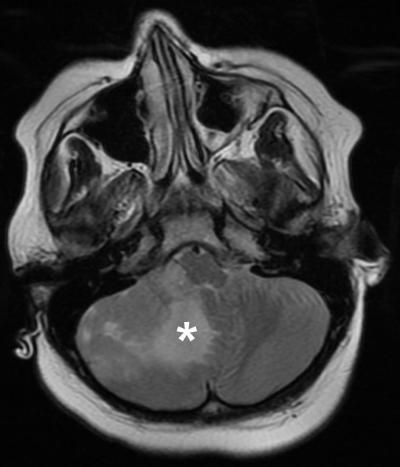

Photo: A test run of the personalized drug screen was completed using a brain tumor from an 8-year-old boy newly diagnosed with metastatic medulloblastoma. An information package about his tumor, including…

To confirm that this approach could be used in the real world, the scientists completed a “test run” using a brain tumor removed from an 8-year-old boy newly diagnosed with metastatic medulloblastoma. A personalized drug screen identified several drugs that may work for his tumor type, and the results were reviewed by a molecular tumor board–a panel of physicians and scientists who work together to discuss treatment options. Although per protocol, the child continued with standard-of-care treatment, the results showed that a personalized treatment plan could have been created in time to guide care decisions.